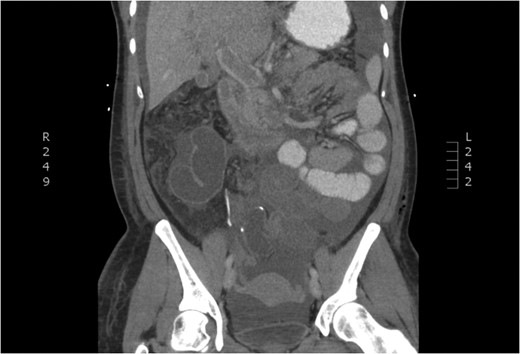

CT of dilated portal vein and extension of thrombosis (axial view).

The patient presented to the emergency room the evening of POD 3 with emesis and obstipation. Her vital signs and laboratory values were normal. An x-ray showed small bowel dilation and she was readmitted for postoperative ileus. A nasogastric tube was placed and the patient was started on IV fluids. Upon worsening pain and tachycardia on POD 4, a computed tomography (CT) scan with triple contrast was obtained. The CT scan showed evidence of PVT (Figs 1–3). The patient was transferred to the ICU and started on a therapeutic heparin. She improved clinically and was discharged home with rivaroxaban on POD 8. A hematologic evaluation was negative for disorders of factor V Leiden, antithrombin III, homocysteine and cardiolipin.